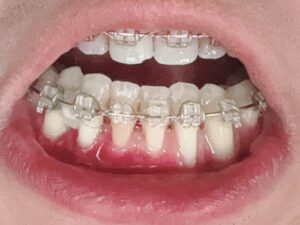

2020年8月15日:矯正器具の装着

歯肉移植手術1回目(手術方式:CBCT、術部:左下2番・3番、手術時間1.5時間)

歯肉移植手術2回目(手術方式:ADM、術部:左下2番・3番と右下2番・3番、手術時間2時間)

歯肉移植手術実施後、下左右にある抜歯跡を埋める作業を再開し、その後矯正器具を外すという流れになります。矯正器具を外した後は、後戻りを防ぎためにリテーナーを作成します。

歯列矯正を中断する(矯正器具は装着したまま)→矯正器具を外す前に歯肉移植手術を2回に分けて実施する。→歯列矯正を再開し、抜歯跡を埋めた後、矯正器具を外し、FIXEDタイプ(取り外し不可)とESSIXタイプ(取り外し可)をつける。